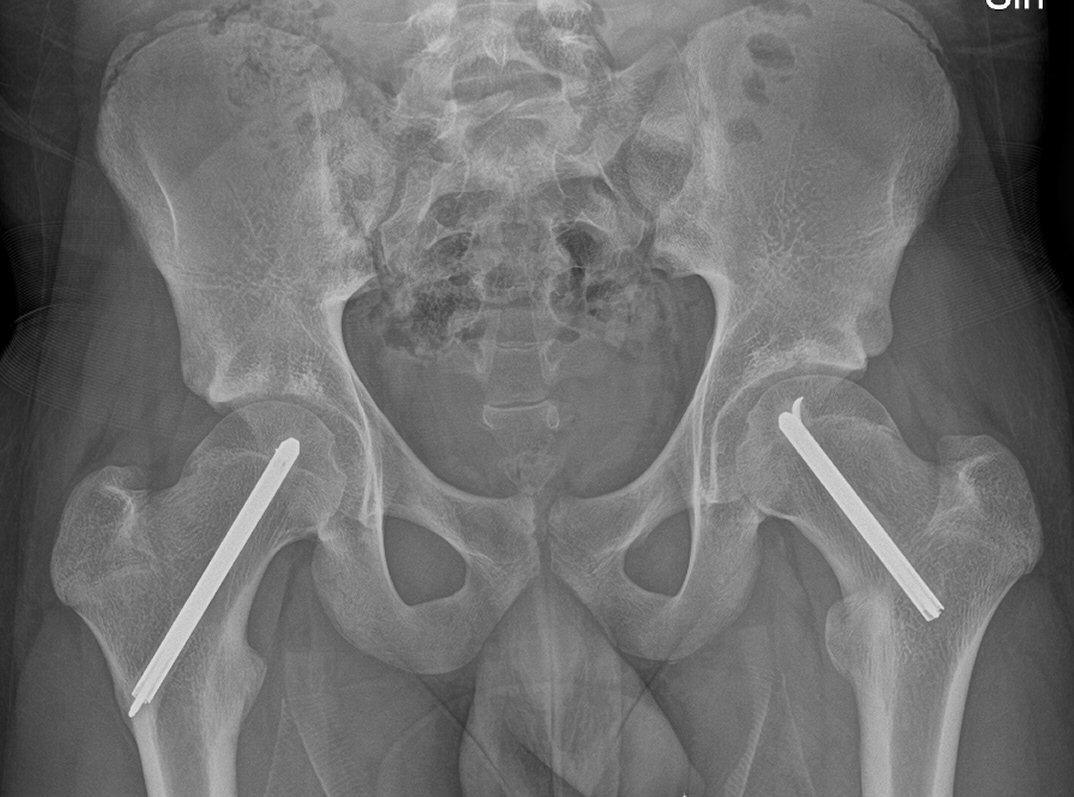

Fysiolys vänster höft akut, efter primär operation resp. innan spikextraktion efter 6 år

- T.ex. LIH-spikning med 1 eller 2 spik, incision betydligt mer anteriort än vanligt, spikarna riktas mer posteriort [3]

- Ofta profylaktisk spikning kontralateral sida pga. upp till 80 % risk för bilateral fyseolys [3]

- Extraktion av spik/spikar efter att fysen slutits [3]